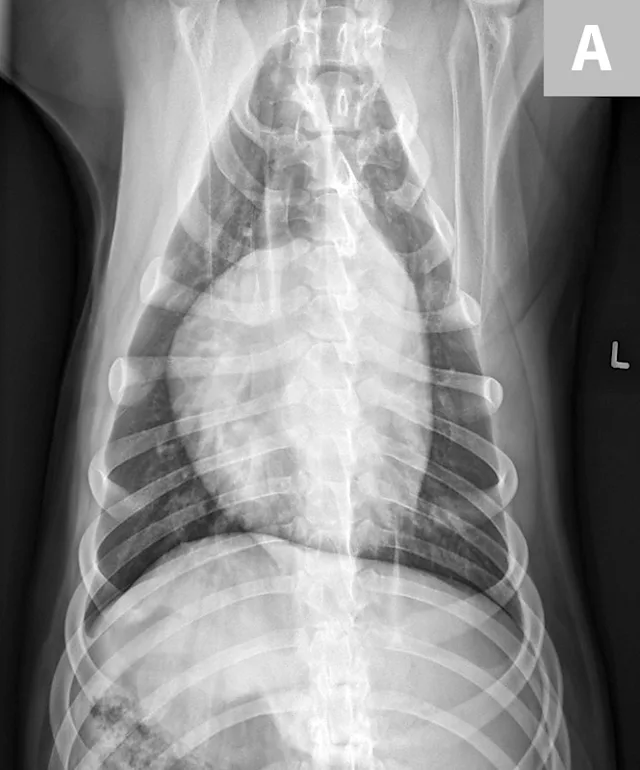

• Make sure the sternum and dorsum are superimposed on the radiograph. If the spinous processes are visible pointing to one side, move the sternum in the direction they are pointing to straighten the spine and sternum. (See Figure 5.)